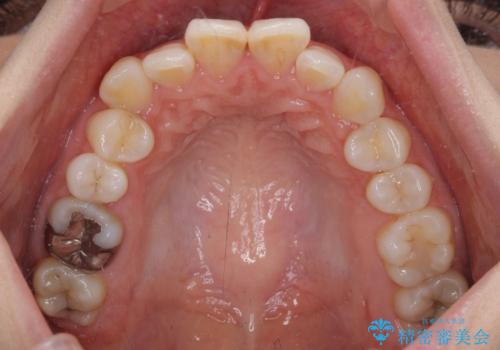

- 上下前歯のデコボコを改善したいとのことで来院された患者様です。

初めの1年くらいは何とか頑張って装着してくださいましたが、途中から変化をあまり感じられなくなり、日々の装着時間は徐々に短くなってしまいました。

前歯のデコボコはもっと改善できましたが、3年半が経過し、初診時と比べたら大幅に良くなったとのことで終了することとなりました。